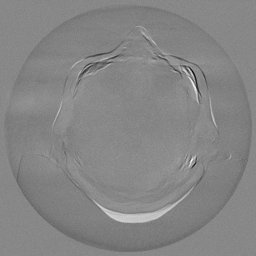

The results for simulated noisy data are shown in Fig. 2. The first and third rows display two representative slices from the test set, and the second and fourth rows present the corresponding error maps. The traditional WCE method suppresses cupping artifacts and recovers some missing anatomical structures but still shows noticeable deviations from the ground truth. Predictions from the four diffusion-based models demonstrate a markedly improved ability to restore anatomical structures. Among them, cDDPM fails to fully reconstruct the patient bed and retains residual noise in its outputs. This noise is attributable to an incomplete reverse denoising process rather than residual Poisson noise, as evidenced in our noise-free experiments (Fig. 5 in the Appendix). PatchDiffusion, diffusionGAN, and I2SB achieve similar visual quality, with I2SB producing the cleanest and most consistent reconstructions.

Quantitative results in Tab. V further confirm I2SB’s superiority over conventional deep learning methods such as FBPConvNet and Pix2pixGAN across RMSE, PSNR, and SSIM. Compared to other diffusion models—including cDDPM, PatchDiffusion, and cLDM—I2SB delivers higher image quality, while diffusionGAN achieves comparable quantitative performance. However, I2SB demonstrates a significant advantage in inference efficiency, as summarized in Tab. IV.